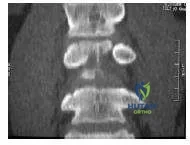

Question 14:

A 70-year-old man complains of severe, burning pain in both calves after he ambulates approximately one block. He denies significant back pain. He has long-standing, insulin-dependent diabetes mellitus and a history of coronary artery disease. The patient has smoked two packs of cigarettes each day for more than 30 years. A magnetic resonance image (MRI) of the patient is obtained, as well as a myelogram (Slide). Conservative options in this patient include:

Options:

- Medication

- Epidural steroids

- C onditioning exercise

- All of the above

- None of the above, proceed to surgery

Correct Answer: All of the above

Explanation:

The myelogram confirms the diagnosis of lumbar spinal stenosis at L3-L4 and L4-L5. There is no myelographic block, although the stenosis is significant. A trial of conservative therapy is appropriate for this patient.